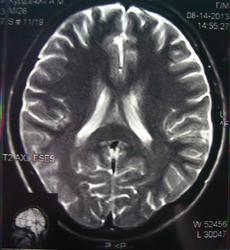

При изучении МРТ снимков головного мозга невролог указала на наличие маленьких очажков на коре головного мозга, порекомендовав обратиться за лечением к нейрохирургам. Голова также продолжает болеть, еще стали кисти рук неметь и прочие симптомы. Можете ли вы указать, имеются ли эти маленькие очажки на коре головного мозга и где именно?

Алексей, очагов достоверно не вижу, а вот на верхнечелюстную пазуху нужно обратить внимание-есть ее воспалительные изменения в виде утолщения слизистой.